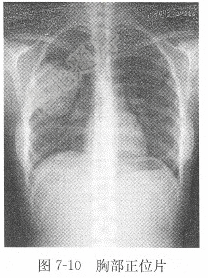

试题详情单项选择题女性,68岁,胸痛1月,X线影像见图7-10,X线诊断为( )。A、右上肺癌B、右上肺结核C、右上肺脓肿D、右上肺炎正确答案:关注下方微信公众号,搜题查看答案热门试题心室颤动上、下消化道造影脑梗死窦性心动过速检查女性,28岁,胸痛半月,X线图像见图7-γ-谷氨酰转移酶(GGT)脑脊液常规血清钠参考值血清无机磷血清铁测定尿常规肺炎血清总蛋白、白蛋白(A)、球蛋白(G)及血清总钙肌酸激酶同工酶急性胰腺炎如何判断房性期前收缩代偿间歇是否完全?题见图6-10。 肾癌脑出血